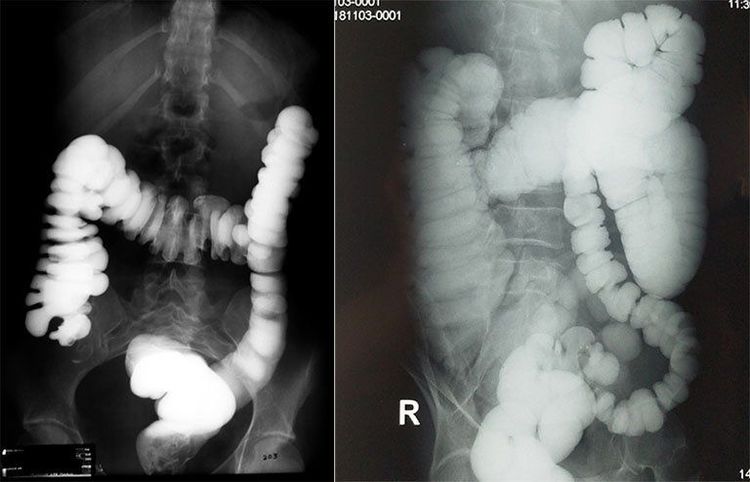

- Rút dây dẫn, sau đó bơm thuốc cản quang tan trong nước giúp đánh giá mức độ và vị trí hẹp.

- Bơm thuốc cản quang qua ống thông để xác định mức độ, vị trí và chiều dài đoạn hẹp.